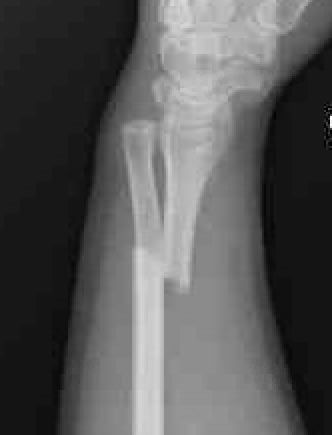

Shortening of radius with disruption of DRUJ on lateral

Concern for disruption of DRUJ on lateral

1. Anatomical ORIF of distal radius with dynamic compression plate

- anatomical reduction

- restoration of radial bow

- compression for healing

Radius ORIF with dynamic compression plates